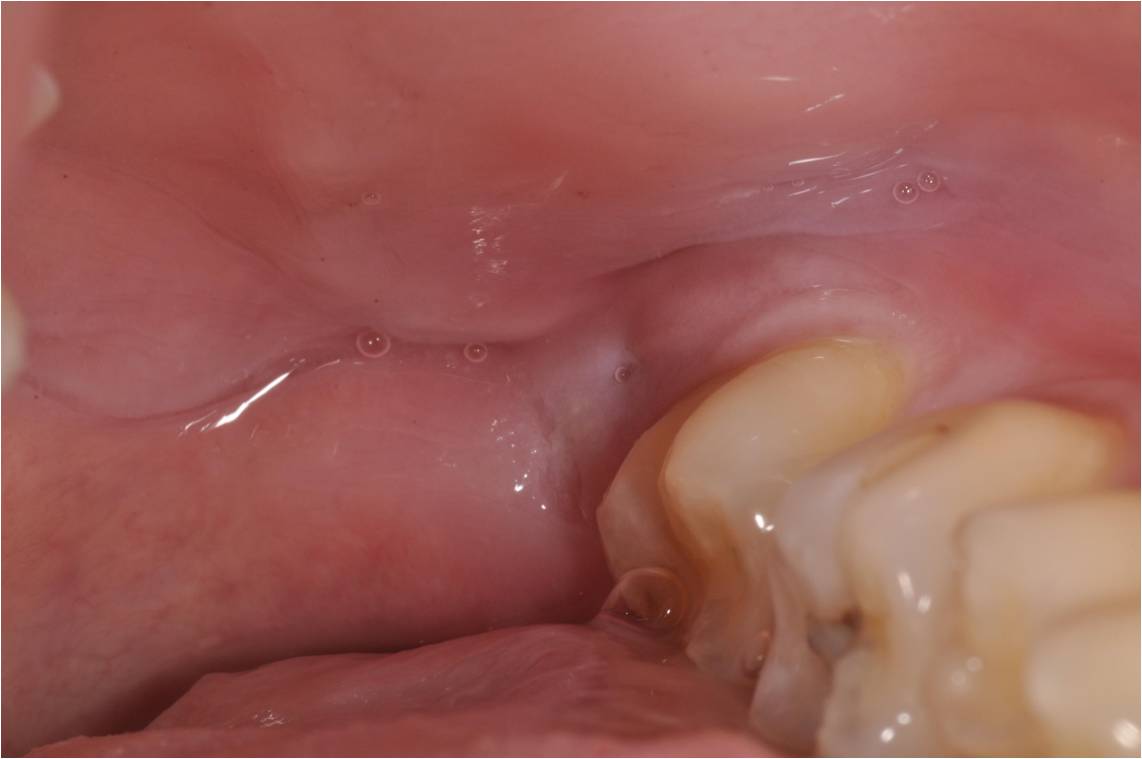

治療前,阻生齒牙齦經常腫脹